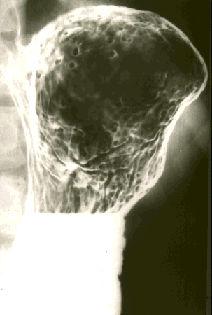

[Image-ID:125]

대장 선종증(가족성 대장 용종증 및 Gardner증후군)/

위(부위)/궁륭

X-P